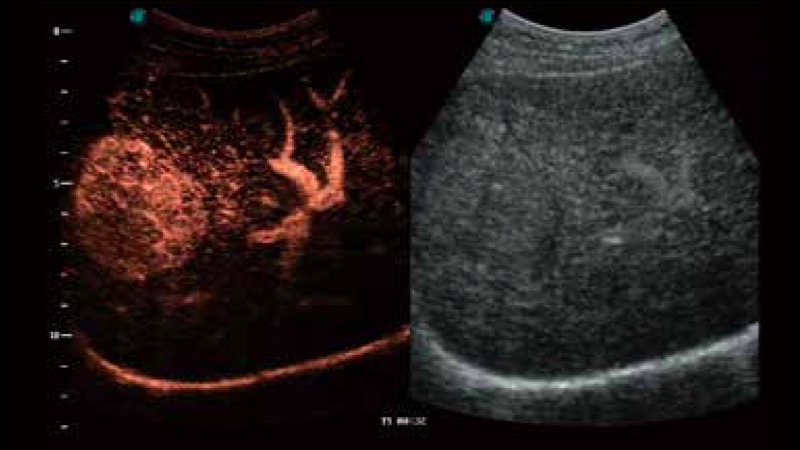

凭借狗万官方网站先进的成像技术和优异的探头技术提供的清晰的图像表现,您可以更自信地做出临床决策。